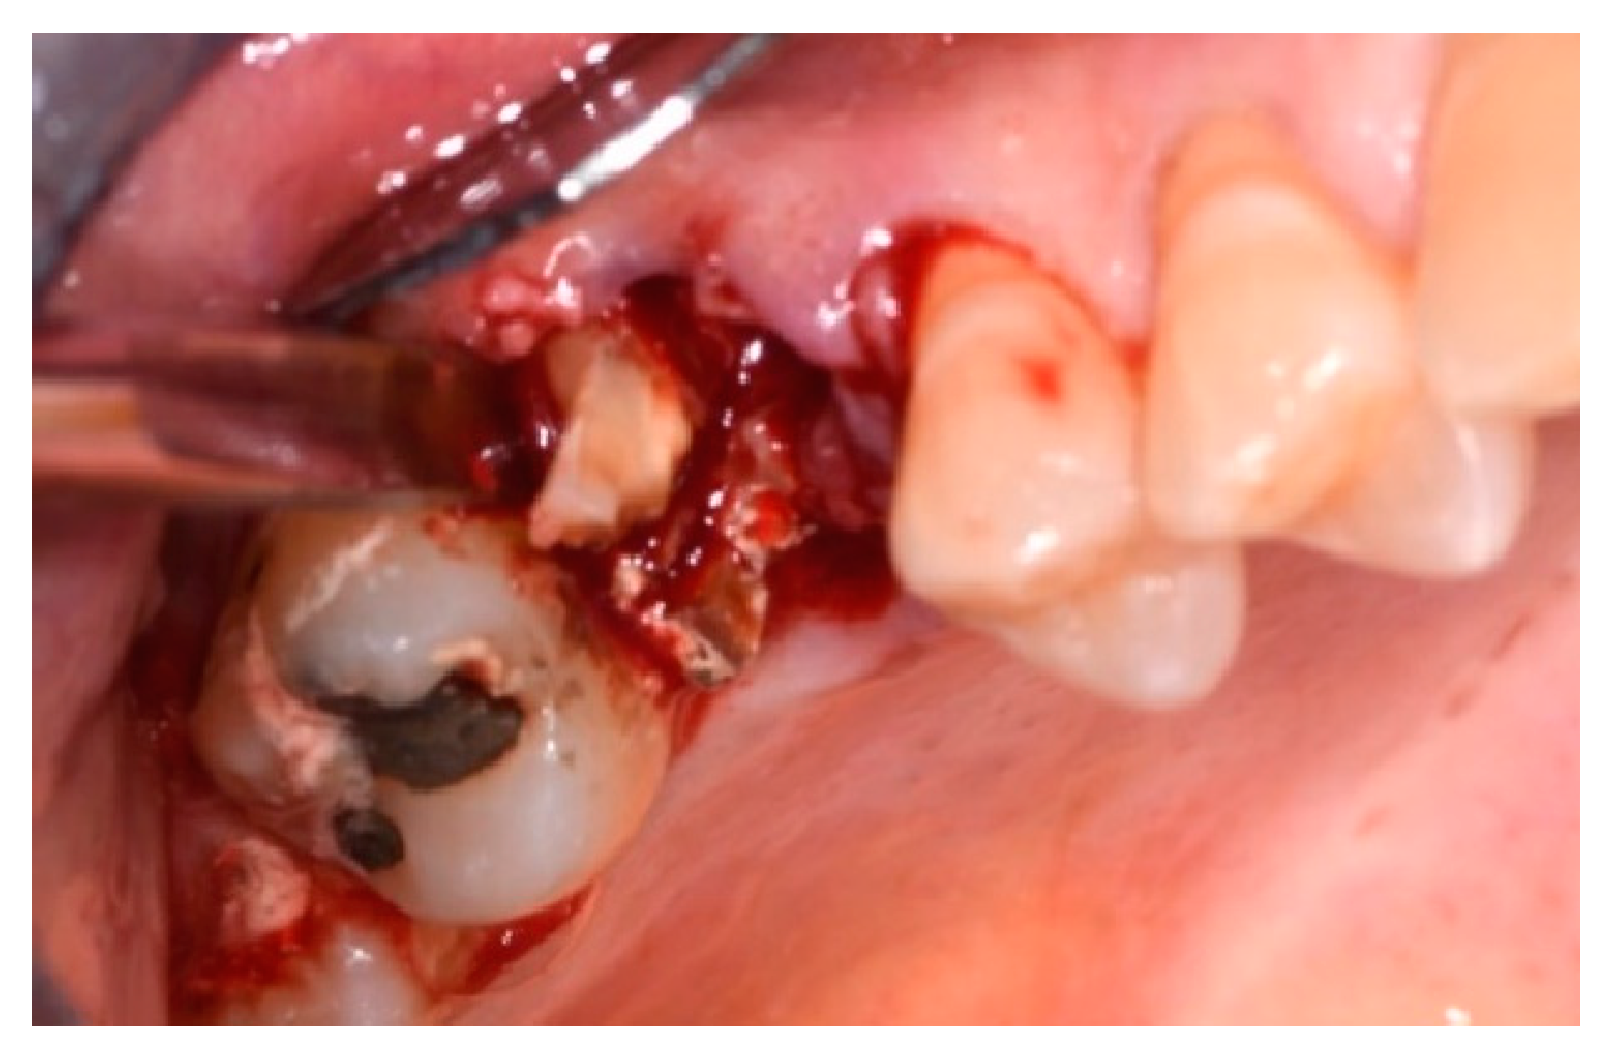

- Presence of at least one severely compromised dental element to be extracted;

- Cause of extraction: caries, orthodontic reasons, or trauma;

- Measurement in mm of the depth of insertion of the instrument into the gingival sulcus;